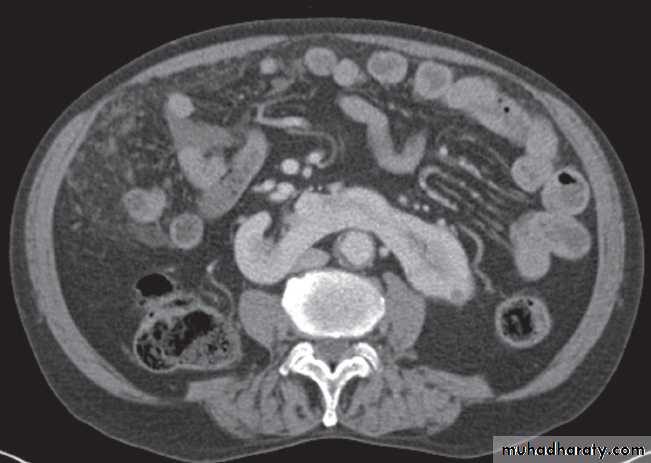

There are many varieties of cystic renal disease varying from simple cysts, which may be single or multiple, to complex renal dysplasias. The most frequent complex dysplasia encountered in clinical practice is autosomal dominant polycystic kidney disease.Renal agenesis